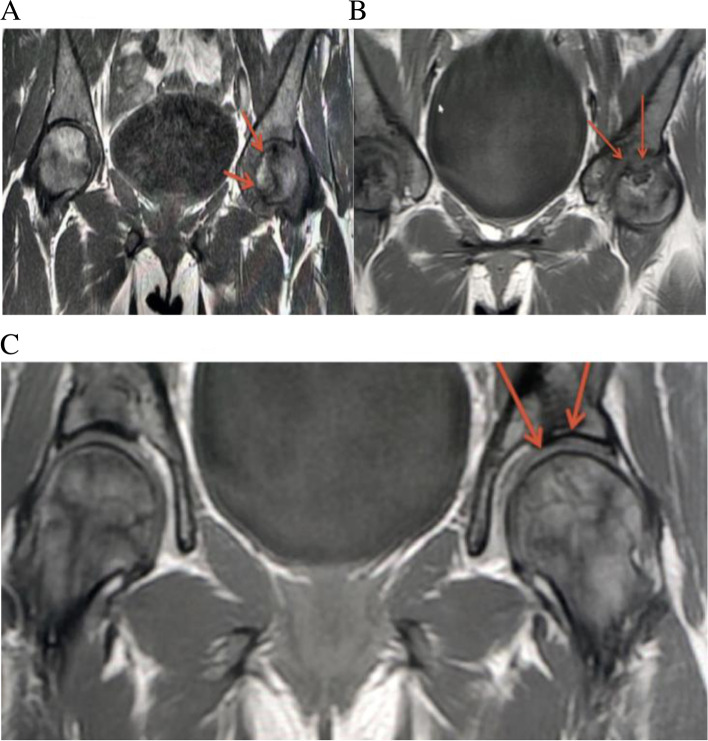

Fig. 3.

A Coronal T1 fat suppressed image of the pelvis demonstrates a geographic area of abnormal signal intensity in the left femoral head (red arrows) compatible with ANFH. B Coronal T1 weighted image performed 4 Months after demonstrates interval improvement of ANFH as well ghost tracts from prior drilling through which osteoblasts were transplanted (red arrows). C Coronal Short-TI Inversion Recovery weighted image performed 18 Months after demonstrates further interval improvement in surface area involvement of the left femoral head involvement by ANFH (red arrows). D Coronal Short-TI Inversion Recovery weighted image performed 36 Months after demonstrates complete resolution of the femoral head ANFH (red arrows)

Overall, 59 (93.6%) patients were satisfied with their improved quality of life, and 4 (6.4%) were unsatisfied, as their disease progressed and they had to have THA (Table 3). The failure of the 4 patients could be due to the occlusion of the vascular supply to the head of the femur due to a vaso-occlusive crisis, and the patients had a hemoglobin S of 92% and Ficat grade III. A comparison of the MRI’s from before and after the osteoblast implantation revealed new bone formation and amelioration of the avascular lesions (Figs. 1, 2 and 3).